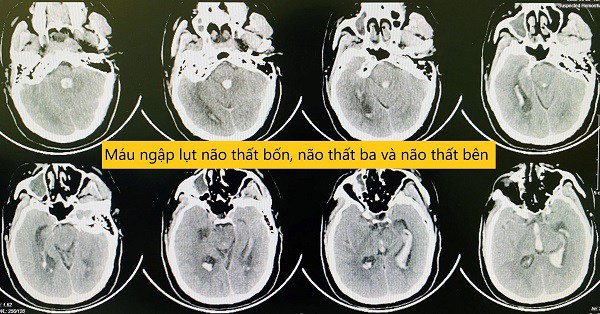

Hình ảnh máu ngập lụt trong não bệnh nhân. Ảnh: BSCC.

Kết quả cho thấy hình ảnh máu ngập lụt hết toàn bộ não thất bên, não thất ba, não thất tư gây giãn não thất cấp, gây tắc nghẽn sự lưu thông hệ thống não thất. Với mức độ tổn thương này nếu không làm gì gần như chắc chắn sẽ tử vong.